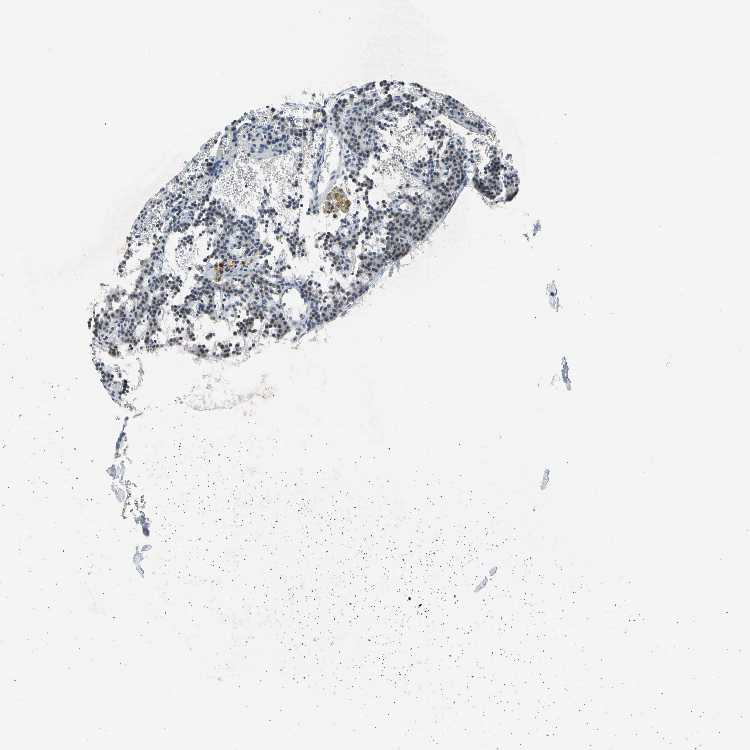

PARATHYROID GLAND - Antibody stainingi

Antibody staining in the annotated cell types in the current human tissue is reported as not detected, low, medium, or high, based on conventional immunohistochemistry profiling in selected tissues. This score is based on the combination of the staining intensity and fraction of stained cells.

Each image is clickable and will lead to virtual microscopy that enables deeper exploration of all samples and also displays staining intensity scores, fraction scores and subcellular localization as well as patient and tissue information for each sample.

Antibody HPA007863Antibody CAB002226

Glandular cells Not detectedNot detected